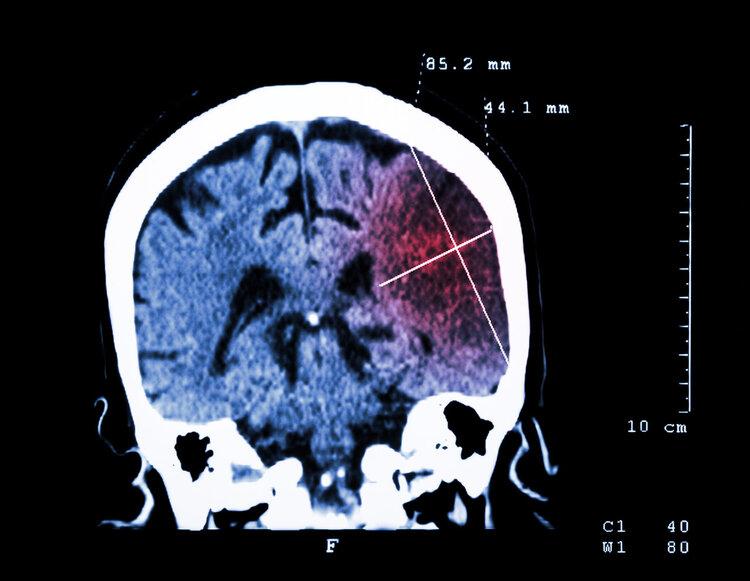

午睡醒來後,王阿姨發現自己連水杯都端不穩,走路時右腿直打晃。見休息也不能緩解,王阿姨心生不妙,趕忙讓老伴帶着她醫院。送醫後,CT顯示她已突發大面積腦梗。